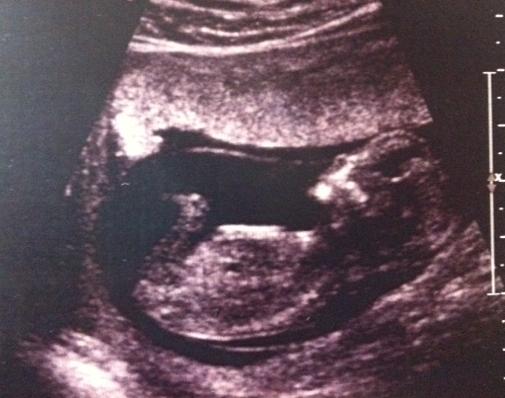

This is our first baby and I am dying to know the gender. Please see attached a few photos from our 12 week scan. What do you think - boy or girl????